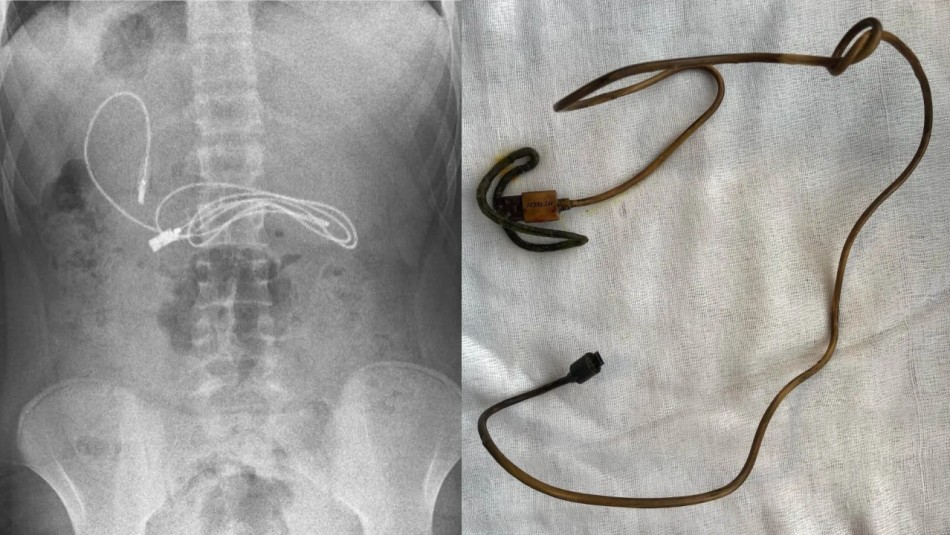

Tras observar los resultados, los médicos quedaron sorprendidos al encontrar un cable, que pertenecía al cargador de los audífonos del menor, dentro de su estómago.

Finalmente, tras lograr extraer todo el cable que se mantenía enrollado al interior del joven, los profesionales lograron constatar que este medía casi un metro de largo y, además, descubrieron y extrajeron una cinta para el pelo al interior del menor. Sin embargo, al ser consultado, el muchacho no reveló cómo o por qué consumió los objetos.